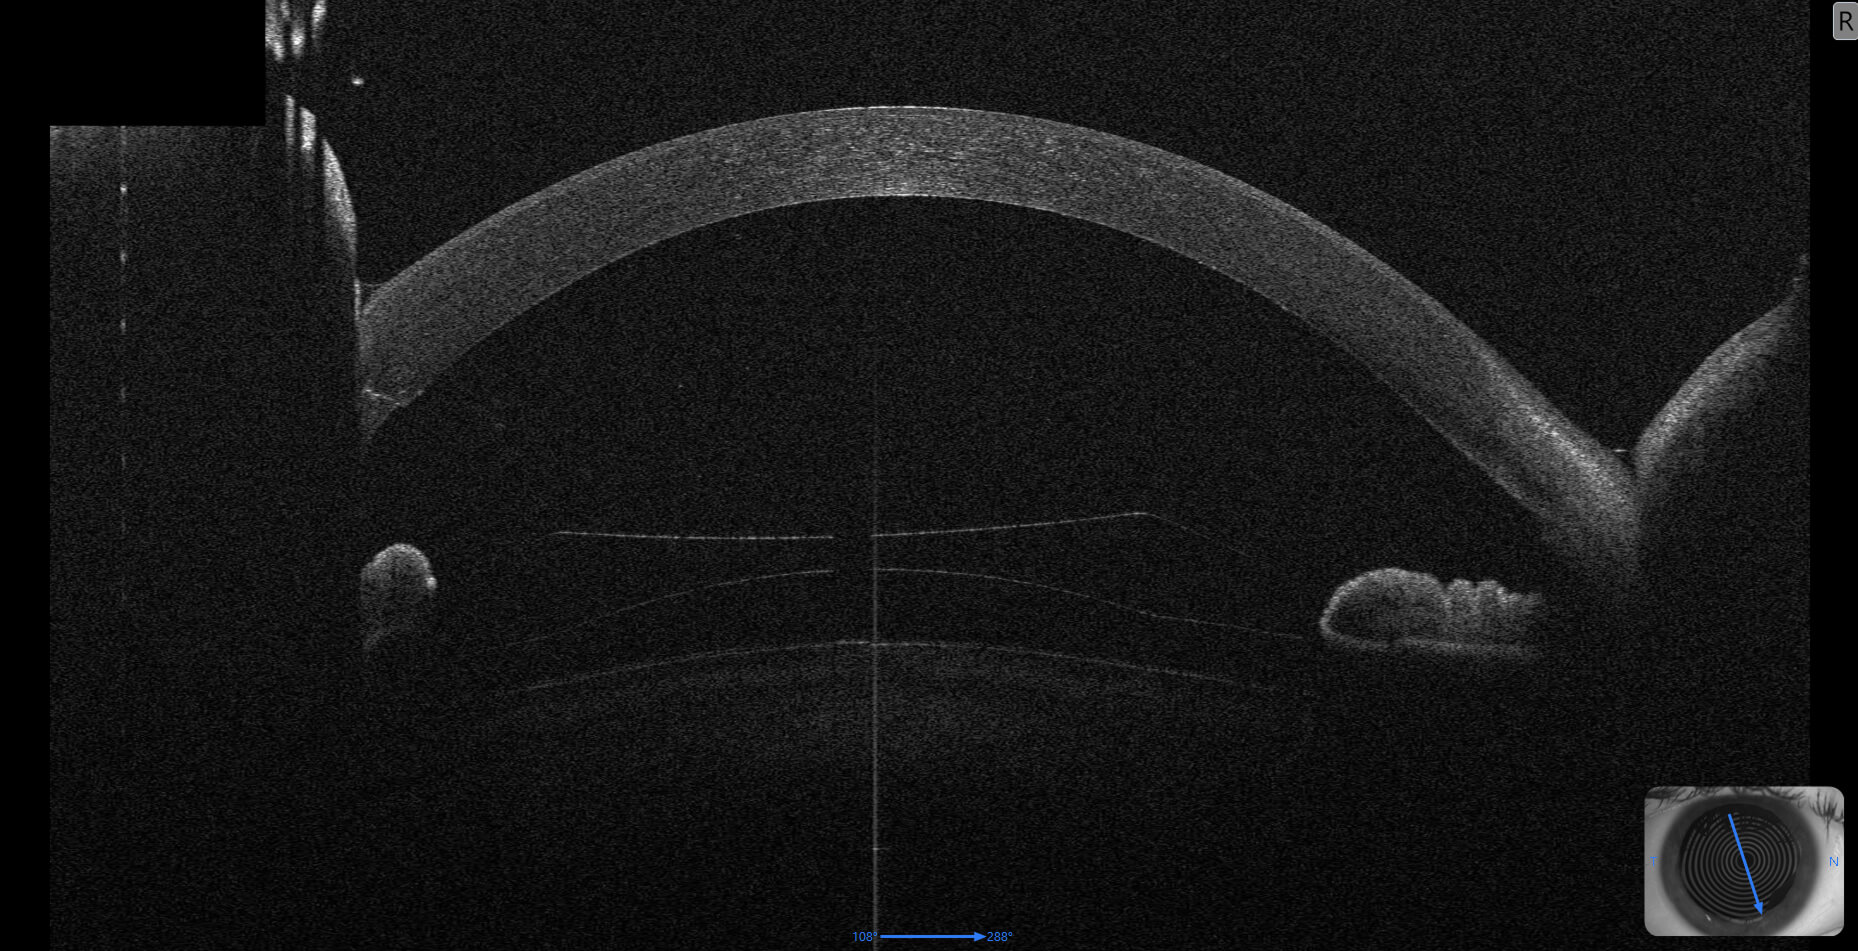

Eine besondere Herausforderung ist die exakte Durchmesserberechnung der Linse, da diese individuell an die Anatomie des Auges angepasst werden muss. Vor der Operation werden daher mehrere hochpräzise Messungen mit zwei unterschiedlichen modernen Vorderabschnitt-OCT-Geräten durchgeführt. Mithilfe neuer, teils KI-gestützter Algorithmen kann die Linsengröße genauer bestimmt werden als mit dem herstellerbasierten Standardverfahren. Zusätzlich wird sorgfältig geprüft, ob die Anatomie des Auges für diese Operation geeignet ist – unter anderem durch Endothelzellfotografie, die ebenfalls in der Ordination von Prof. Findl durchgeführt wird.

Die ICL muss in ihrem Durchmesser exakt zur individuellen Anatomie des Auges passen. Eine präzise Berechnung ist entscheidend für Sicherheit und Langzeitergebnis. Daher werden vor der Operation mehrere hochpräzise Messungen mit modernen Vorderabschnitt-OCT-Geräten durchgeführt. Prof. Findl verwendet dabei auch neue, teils KI-gestützte Algorithmen, die eine genauere Berechnung ermöglichen als das herstellerbasierte Standardverfahren.

Neben der OCT-Vermessung des Vorderabschnitts wird unter anderem eine Endothelzellfotografie durchgeführt. Damit wird geprüft, ob die Hornhaut für eine phake Kunstlinse geeignet ist. Diese Untersuchungen erfolgen in der Ordination von Prof. Findl.